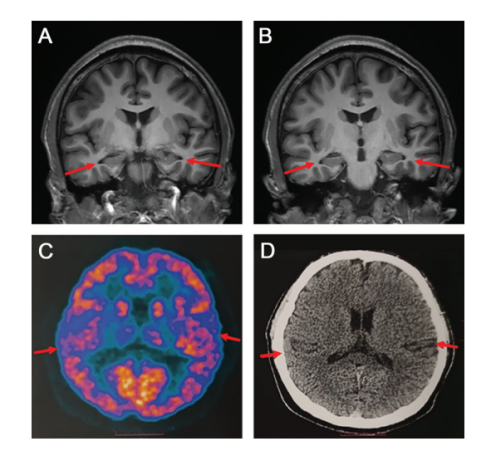

事实上,文中介绍的这名19岁男孩

是阿尔茨海默病迄今为止最年轻的患者

此前虽然确实发现过20多岁罹患阿尔茨海默病的患者,但这类患者往往会存在基因突变或家族史。然而,论文中提出:“但最终经过全面的检查,我们确认这次的患者没有家族史,以现有的手段也无法查到基因突变。这种情况确实极为罕见。”